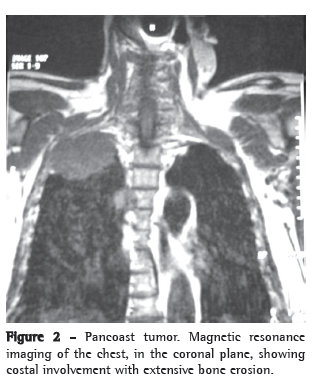

We report a case of a 74-year-old hypertensive white male, a painter, with peripheral vascular insufficiency of the lower limbs. The patient had been a smoker for 54 years (one pack of cigarettes per day). He presented with a two-month history of sharp, right-sided pleuritic pain, accompanied by productive cough with watery expectoration, as well as by dyspnea upon exertion. Physical examination at admission showed only universal reduction in breath sounds, and reduced dorsalis pedis pulse rate, without neurological deficits. No alterations were observed in the results of the blood workup, biochemical blood tests or urinalysis. His PPD was nonreactor and testing for acid-fast bacilli in sputum was negative. Chest imaging tests (Figures 1 and 2) showed a mass with regular borders in the right superior sulcus, affecting the adjacent vertebrae and ribs. Whole-body gallium scintigraphy and CT of the skull were normal. The patient was submitted to thoracic punch biopsy, the histopathological study of which showed small cell lung carcinoma (Figure 3). During his hospital stay, the patient evolved to paresthesia in the right axilla region and worsening of the chest pain, which became intense over the right scapula.

The pulmonary mass was investigated using CT and magnetic resonance imaging of the chest. Even with the advances in CT imaging acquisition techniques, with better detection and evaluation of the tumor growth, as well as of the extent of infiltration into the chest wall and mediastinal involvement,(9) magnetic resonance imaging of the chest is still the best means of evaluating superior sulcus tumors.(10-12) Although magnetic resonance imaging of the chest provides the same information that CT does, it allows better evaluation of the central nervous system impairment.(10)